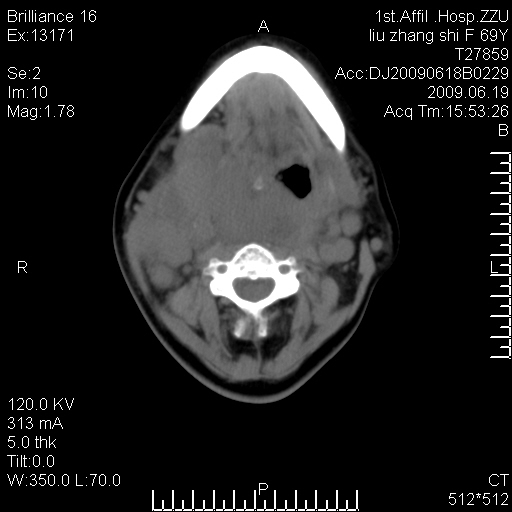

标题: CT26782:女,69岁,颈部占位,3天后公布病理结果。

【病理证实系列】女,69岁,颈部占位,有病理结果,3天后公布。(由于病例时间较久,临床资料不全,请网友见谅)本系列将有几百种常见、少见及罕见病例,均经病理证实。病例资料来自郑州大学第一附属医院。与网友共享,本人有空就发。

甲状腺癌并颈部淋巴结转移。感谢楼主的良苦用心,谢谢。

甲状腺癌并颈部淋巴结转移。

需与鼻咽癌鉴别!

支持甲状腺癌广泛侵及周围结构并颈部淋巴结转移。

鉴别:淋巴瘤、恶性神经源性病变、恶性纤维组织细胞瘤。

病理结果:颈部非霍奇金淋巴瘤。